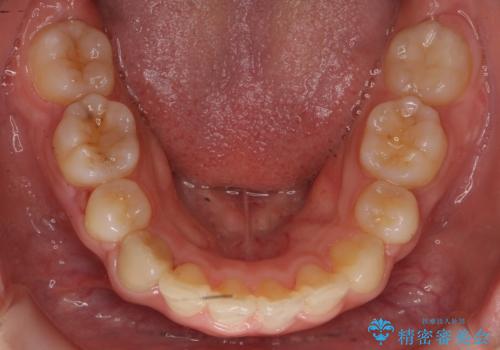

20代女性 出っ歯 口元を引っ込めたい

- 出っ歯と前歯を気にして来院。

口元を下げたいとのことで、歯を抜いてワイヤー矯正を行いました。

上下左右の小臼歯を抜歯しています。